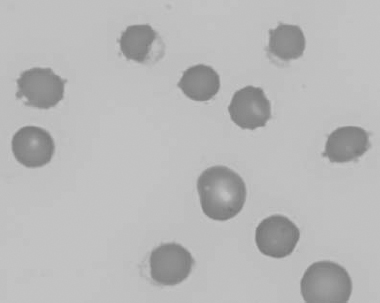

Figure 1.16 Feline blood film showing Mycoplasma hemofelis organisms (hemobartonellosis). Organisms are not always visible in blood smears from infected cats (also see color section).